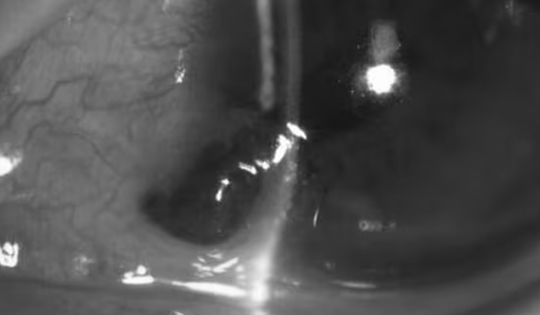

Vi khuẩn lao tấn công màng tim người đàn ông

Vi khuẩn lao tấn công màng ngoài tim khiến anh Tú, 33 tuổi, chán ăn, tiêu lỏng, sụt hơn 3 kg chỉ trong 10 ngày.